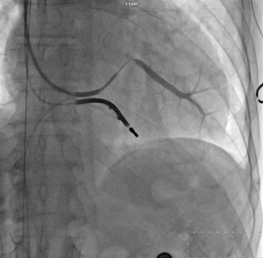

CRT-D成功植入